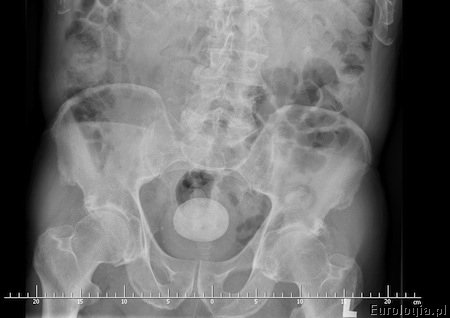

Zdjęcie przeglądowe nerek i pęcherza

Zdjęcie wykonywane jest w pracowni rentgenowskiej w pozycji leżącej. Badanie jest całkowicie niebolesne i nie wymaga żadnego przygotowania ze strony pacjenta. Badanie nie może być wykonywane w diagnostyce kamicy pęcherza moczowego u kobiet podejrzewających ciążę lub będących w ciąży. Zdjęcie przeglądowe jamy brzusznej ma ograniczoną wartość w przypadku złogów zbudowanych z kwasu moczowego. Kamienie moczowe zbudowane z kwasu moczowego są przezierne dla promieniowania rentgenowskiego - są niewidoczne na zdjęciach.

Fot. RTG przeglądowe z widocznym złogiem w pęcherzu moczowym